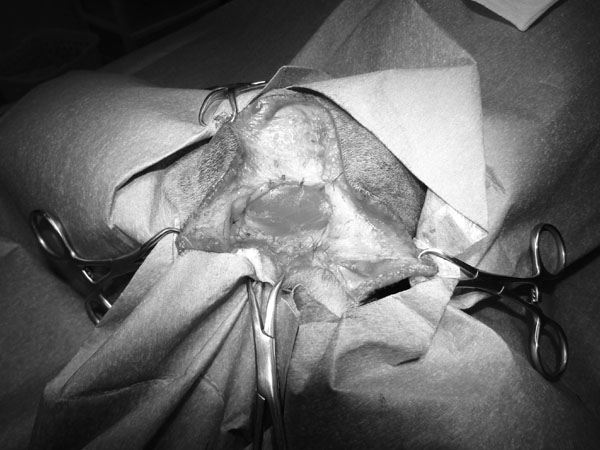

5~6歳以上の去勢手術をしていないオス犬に多い病気ですが、メス犬や去勢した犬に起こることもあります。お尻の筋肉が萎縮した結果、筋肉の隙間から直腸や膀胱が皮膚の下にとびでてしまいます。これにより便が出にくくなったり膀胱炎になったりします。手術をすることで機能回復および今後の致死的な状況を回避することができます。当院では去勢手術→結腸固定→前立腺固定→骨盤隔膜構成筋の縫縮→内閉鎖筋フラップ→浅臀筋フラップの順で通常腹側・臀部左右両側同時に行います。また老化以外に、筋肉が萎縮する原因があったり、腹圧がかかる原因があったりする場合も多いので、再発防止のためそれらの診断・治療も重要です。今回のワンちゃんも無事手術も終わり元気に退院しました。よかったね。